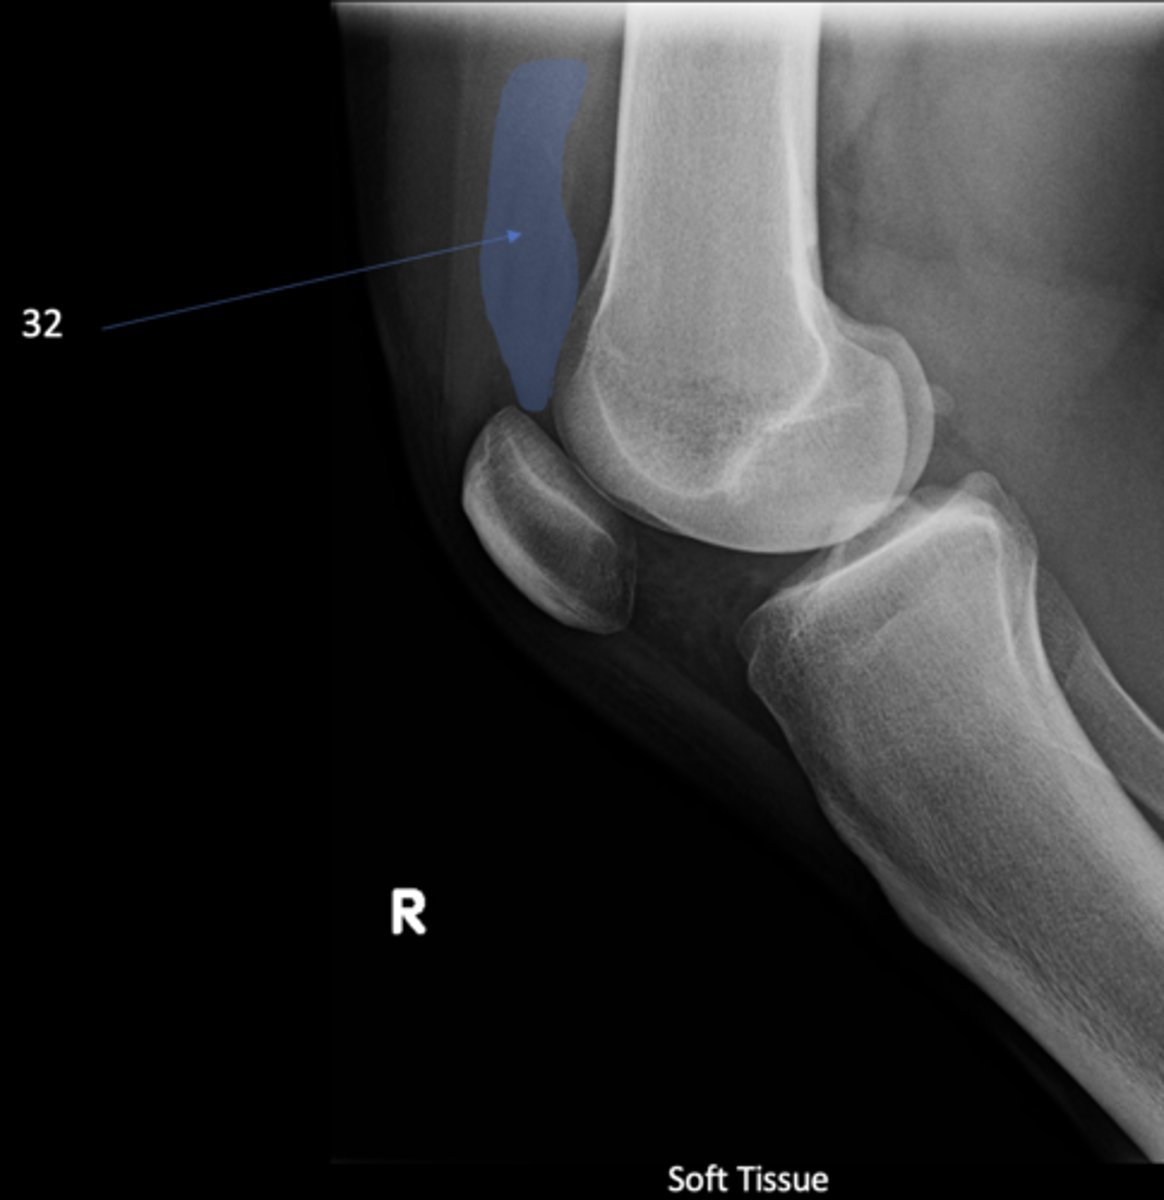

Suprapatellar pouch

ID 32

<p>ID 32</p>